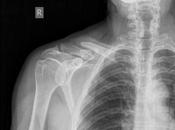

Fractura antigua entre el tercio distal y medio de clavícula derecha con...

RADIOGRAFIA AP DE HOMBRO EN LA PROYECCION RADIOGRÁFICA OBTENIDA, NOS MUESTRA LOS SIGUIENTES HALLAZGOS: Tejidos blandos, con aumento la densidad en topografía... Leer el resto

El 23 febrero 2025 por Godieboy